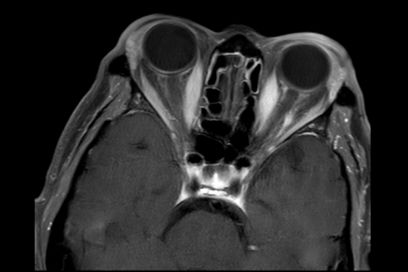

影像学检查:MRI

2.眼部体征不明显的病例需密切关注影像学变化,有时CAS评分与影像学表现不相符。

5.TAO还需与其他以眼外肌增粗,或泪腺增大为影像学表现的疾病鉴别,如眼眶肌炎,IgG4眼眶病等。